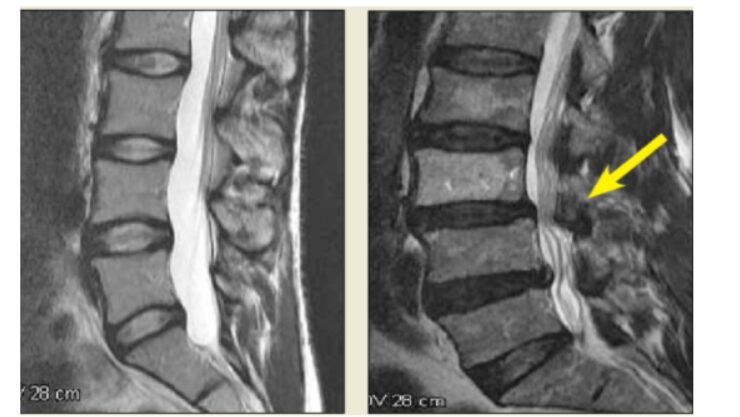

背骨は、椎骨という骨が積み重なってできています。この椎骨には穴が開いており、その穴が縦に連なることで、一本のトンネルのような構造を作っています。これを「脊柱管」と呼びます。

この脊柱管というトンネルが何らかの原因で狭くなり、中を通る神経や血管が圧迫される状態が、脊柱管狭窄症です。

加齢とともに、背骨を支える靭帯が厚く硬くなります。特に、黄色靭帯という脊柱管の後ろ側にある靭帯が肥厚すると、脊柱管を後ろから圧迫します。

椎間板は、年齢とともに水分を失い、薄くなります。すると、椎骨同士の間隔が狭くなり、脊柱管も狭くなります。また、椎間板が後方に突出すると、前からも脊柱管を圧迫します。

背骨の関節である椎間関節が変形すると、骨棘という骨の出っ張りができます。これが脊柱管の中に突出すると、神経を圧迫します。